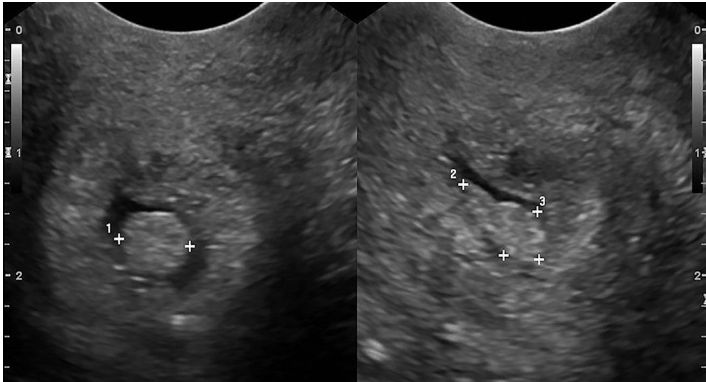

1?

Intramural

2?

Pedunculated

3?

Intracavitary

4?

Suberous

5?

Submuscosal